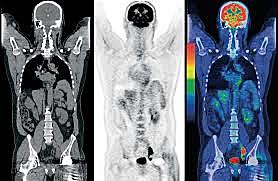

• Exploración PET-CT

Exploración PET-CT

Ronald Nutt y David Townsend inventan la exploración PET-CT que combina la tomografía por emisión de positrones y la tomografía computarizada de tal manera que facilita a los médicos la localización de tumores y otras estructuras en las imágenes. Al combinar estos dos escaneos en una sola máquina, también hicieron que fuera mucho más fácil y menos costoso para los médicos y hospitales tener acceso a ambas formas de tecnología